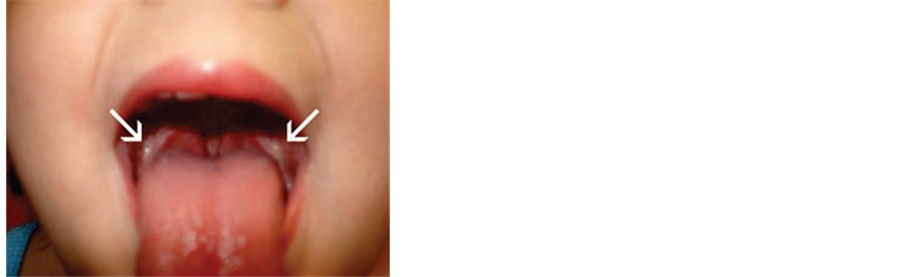

The following figures represent an enlargement in the adeno-tonsillar tissue (Figure 2) and a massive uvula [2] .

Figure 2. Adenotonsillar hypertrophy [2] .